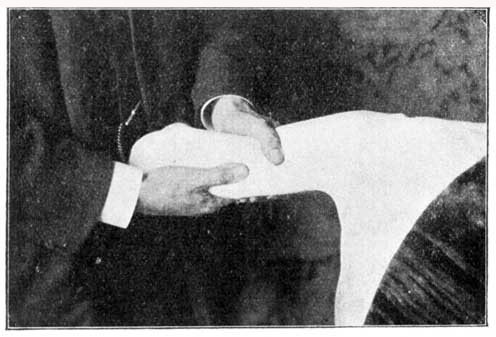

Prepare a bed (long enough for the patient to lie at full length upon his back), with a large thick sheet folded on the lower part of it. Spread over this sheet a blanket wrung out of hot water, so as to be both moist (but not wet) and warm (see Fomentation). See that the blanket is not so hot as to burn the patient and add to his pain. It must be tested with the back of the hand, and be just as warm as this can well bear. On this let the patient lie down, and wrap him up tightly in it from the feet up to above the haunches. Have two or three towels folded so as to be about six inches broad, and the length of that part of the patient's spine above the hot blanket. Wring these out of cold water. Place one over the spine, so as to lie close along it; on this, place a dry towel to keep the damp from the bed, and let the patient lie down on his back, so as to bring the cold towel in close contact with the spine. When this towel becomes warm, another cold one must be put in its place. After about half an hour's pack and eight changes of the cold towel, the pain in the chest should be subdued for the time. If the cold towel does not heat in five minutes, the patient's vitality is low, and a hot cloth should be placed along the spine, and renewed several times, and then another cold one; but as a rule this will not be required. When taken out of the pack, let the skin be washed with soap (see) and warm water; then a slight sponge of nearly cold water, and a gentle rubbing with olive or almond oil. Rub the back first, and gently "shampoo" all the muscles; that is, knead and move the muscles under the skin so as to make them rub over one another.